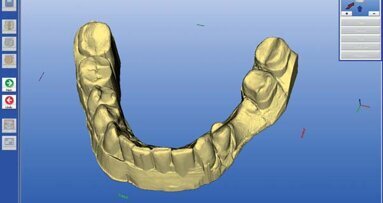

Docięty łącznik na modelu z maską dziąsłową laboratorium przekazało do gabinetu, gdzie następnie na modelu uzupełniłem żywicą przestrzeń pomiędzy łącznikiem a maską dziąsłową (Ryc. 22). Następnie przykręciłem łącznik wg klucza protetycznego w ustach pacjentki i nałożyłem na niego wcześniej przygotowany pierścień z żywicy podpierający dziąsło (Ryc. 23) i doszlifowałem go wiertłami wg standardów preparacji pod korony pełnoceramiczne (Ryc. 24-27). W pracowni pierścień ten został zeskanowany i wg niego zaprojektowano czapkę cyrkonową pod koronę ceramiczną (Ryc. 28 i 29).

Profil ukształtowany przez koronę tymczasową zespoloną z łącznikiem tymczasowym został tym samym precyzyjnie odtworzony w pracy ostatecznej. Taki protokół postępowania był możliwy dzięki pracy w systemie CAD/CAM. Dlatego po zacementowaniu korony na implancie wygląd dziąsła przy nim był bardzo zbliżony do kształtu dziąsła przy zębie jednoimiennym. Różnica w kolorze, która pozostała spowodowana jest niestety, trwałym tatuażem po zaaplikowaniu amalgamatu przed laty.